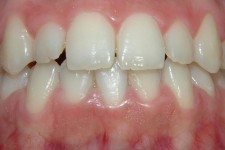

LIJEVO: 1a početno stanje,prednji zubi - DESNO: 1b nakon završetka terapijee LIJEVO: 2a revizija punjenja korijenskih kanala,višekorijenski zubi        <br />